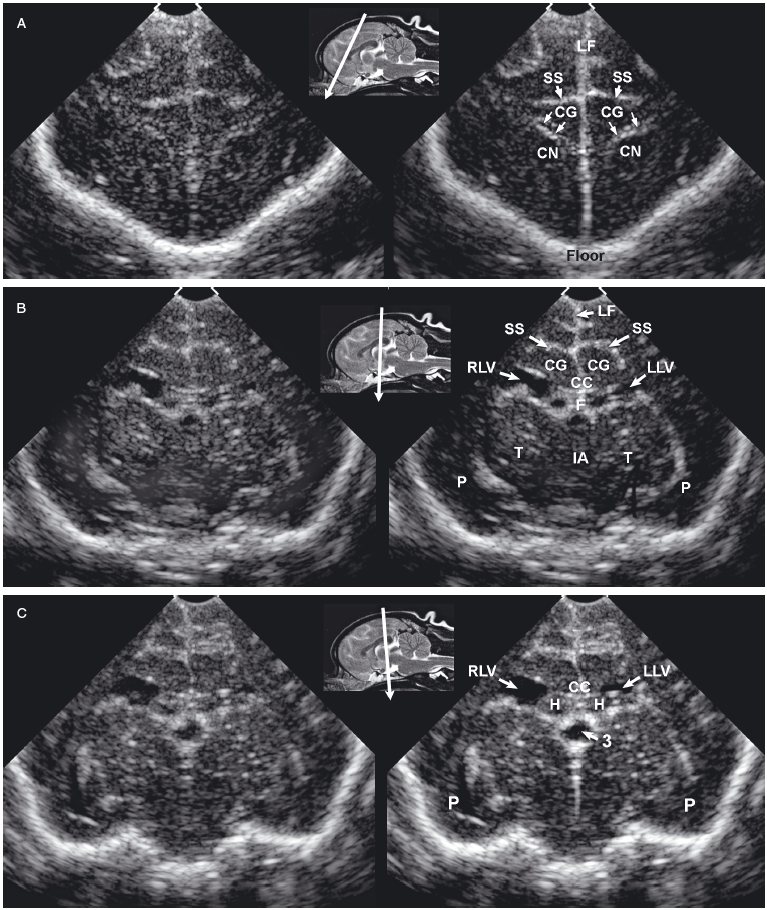

The sonographic anatomy of the brain of normal dogs has been described (Hudson et al. 1989) (Figure 1.3). The longitudinal fissure and splenial sulci form a hyperechoic umbrella-like structure that can be used as a landmark to locate the midline of the brain. This is particularly useful when a natural or created defect in the skull is located asymmetrically. The cingulate gyrus is found deep to each splenial sulcus. Rostrally, the caudate nuclei are recognizable as hyperechoic curved structures. The lateral ventricles are located medial to the caudate nuclei and vary greatly in size according to the breed, age, and individual. Asymmetry is common. Cerebrospinal fluid (CSF) is anechoic and may cause the lateral ventricles to appear as small anechoic slits in some individuals.

Figure 1.3. Transverse sonograms of the brain of a 1-month-old Yorkshire terrier. The ventricles are asymmetrical but within normal limits. A: Rostral sonogram. B: Sonogram at the level of the interthalamic adhesion. C: Sonogram at the level of the third ventricle. D: Sonogram with the ultrasound beam angled caudally to image the mesencephalon. E: Sonogram with the ultrasound beam angled caudally to image the cerebellum. 3, third ventricle; CC, corpus callosum; CG, cingulate gyrus; CN, caudate nucleus; F, fornix; H, hippocampus; IA, interthalamic adhesion; LF, longitudinal fissure; LLV, left lateral ventricle; M, mesencephalon; P, pyriform lobe; Po, pons; RLV, right lateral ventricle; SS, splenial sulcus; Su, subarachnoid space; T, thalamus; and V, vermis.

As the beam is swept slightly more caudally, the rostral fornix comes into view. Choroid plexus is hyperechoic while it lies on the floor of the central portion of the lateral ventricle and the roof of the temporal horn. It may be difficult to distinguish between the caudate nucleus and the adjacent choroid plexus in the lateral ventricle, so only a single hyperechoic focus might be seen on each side of the midline in some dogs. If there is sufficient CSF, the lateral ventricle can be seen.

In older puppies and adult dogs, alternating hyperechoic and hypoechoic lines represent the callosal sulcus, corpus callosum, and fornix. Comparison with histological samples suggests that the most superficial hyperechoic layer is the callosal sulcus, which contains vessels that pulsate. The corpus callosum is comprised of a hypoechoic surface with a deeper hyperechoic border. The fornix is hypoechoic. In the first few days of life, these structures may appear only as a single hyperechoic region. Detail improves as myelination progresses after birth. Most of the brain is uniformly hypoechoic, but the pyriform lobes are visible because of hyperechoic meninges dorsal to each lobe.

When the probe is tilted to sweep the ultrasound beam caudally, the dorsal portion of each hippocampus appears as a hypoechoic structure close to the midline. Dorsolateral to each of these structures, a hyperechoic area represents choroid plexus in each lateral ventricle. Another hyperechoic area is seen in the midline ventral to the level of the dorsal portions of the hippocampi. Depending on the angle of ultrasound section, this hyperechoic area may represent choroid plexus in the dorsal portion of the third ventricle or pia mater that is located more caudally in the adjacent subarachnoid space. Vessels and trabeculae in the subarachnoid space may create a complex of echoes that outline the mesencephalon and cause it to appear as a dome-shaped hypoechoic structure. The petrous temporal bones will create irregular hyperechoic echoes on the floor of the cranium on each side of the midline deep to the hypoechoic pyriform lobes.

More caudally, the osseous tentorium is a hyperechoic structure shaped like an inverted V. In older animals, this structure often prevents visualization of the caudal brain, but the medulla and cerebellum can be imaged in neonatal animals. The medulla is hypoechoic. The vermis of the cerebellum is represented by a stack of hyperechoic lines seen in the midline. Each lateral cerebellar hemisphere is located more laterally as a hypoechoic structure.